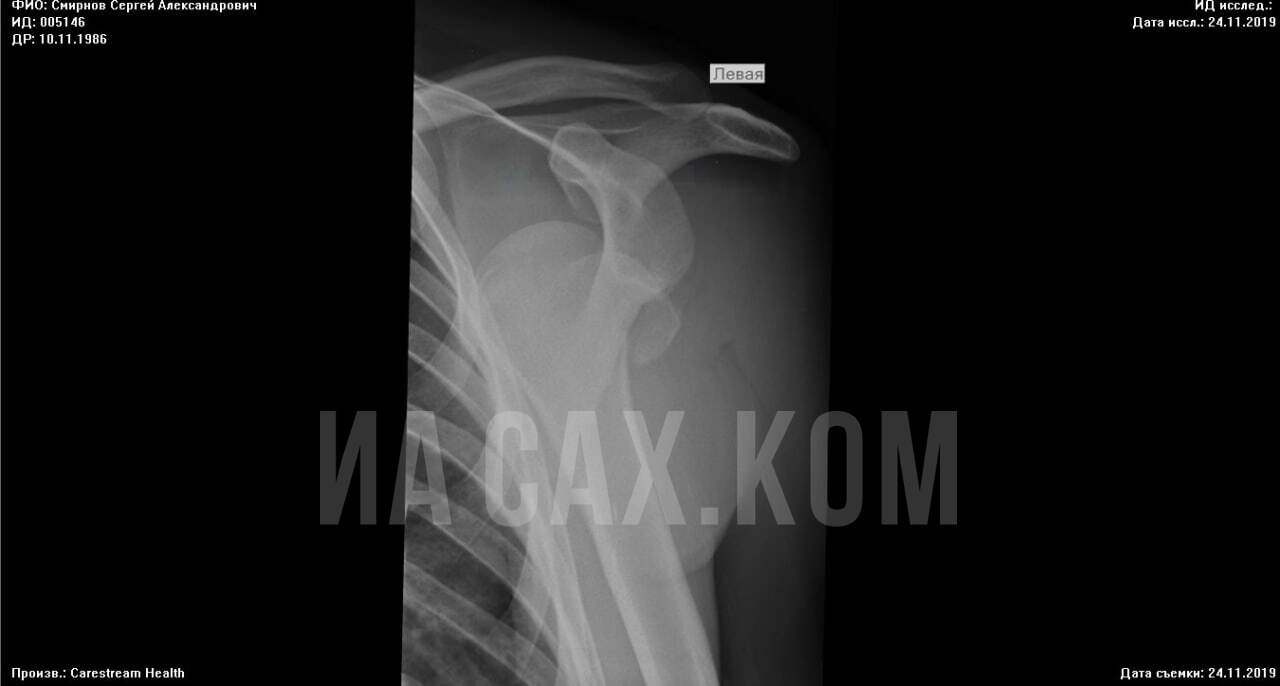

Сергей рассказывает, что мучается с рукой уже три года, она восстановилась процентов на 40 и до сих пор периодически болит. Поднять ее до конца невозможно. На плече огромный шрам. Его Сергей показал во время визита в редакцию ИА Сах.ком, а заодно принес два рентгеновских снимка. Один — сделанный в тот день, когда его привезли на скорой. Там только вывих. Второй — выполненный на следующий день, после того, как хирург "вправил" плечо. Все документы (рентген, решение суда, ответы от минздрава) есть в редакции.

— Сделали рентген, перелома не было, — вспоминает мужчина. — Там было просто смещение, надо было вправить вывих. Поскольку это был выходной, врач-хирург Некруз Зикриёев дежурил дистанционно (Сах.ком уже писал про ургентные дежурства — прим. ред.). Его вызвали, он приехал и под общим наркозом вправил мне руку. Потом разбудил и отправил домой. Я отошел от наркоза — что такое? Спать не могу, опухоль, боль, все обезболивающие дома съел, кое-как дожил до понедельника и пошел на повторный прием утром. Боль была просто адская. Мне сделали снимок, позвали другого хирурга Кимизова, дай бог ему здоровья. Он посмотрел снимок и сказал — нужна экстренная операция. Я спрашиваю, почему. И он говорит, что у меня мелкоосколочные переломы ключицы в двух местах, порвано сухожилие. Сказал, если не сделать срочно операцию, я могу потерять руку. Меня подняли в хирургию, взяли анализы, сделали наркоз и провели операцию. Полторы недели лежал в больнице, потом на свою пенсию покупал таблетки, уколы. Я тогда в похоронном бюро работал, это физическая работа, и в охране тоже. Обе эти работы я потерял.